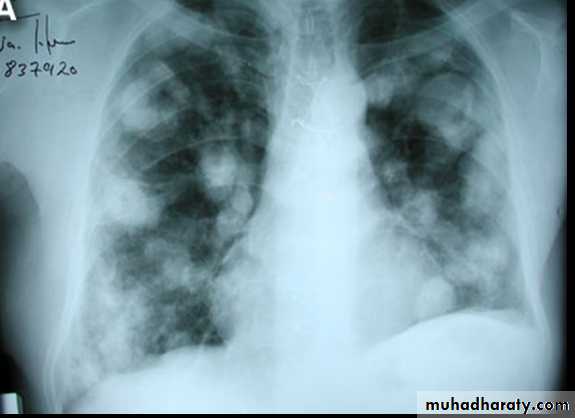

CXR With multiple H.cysts